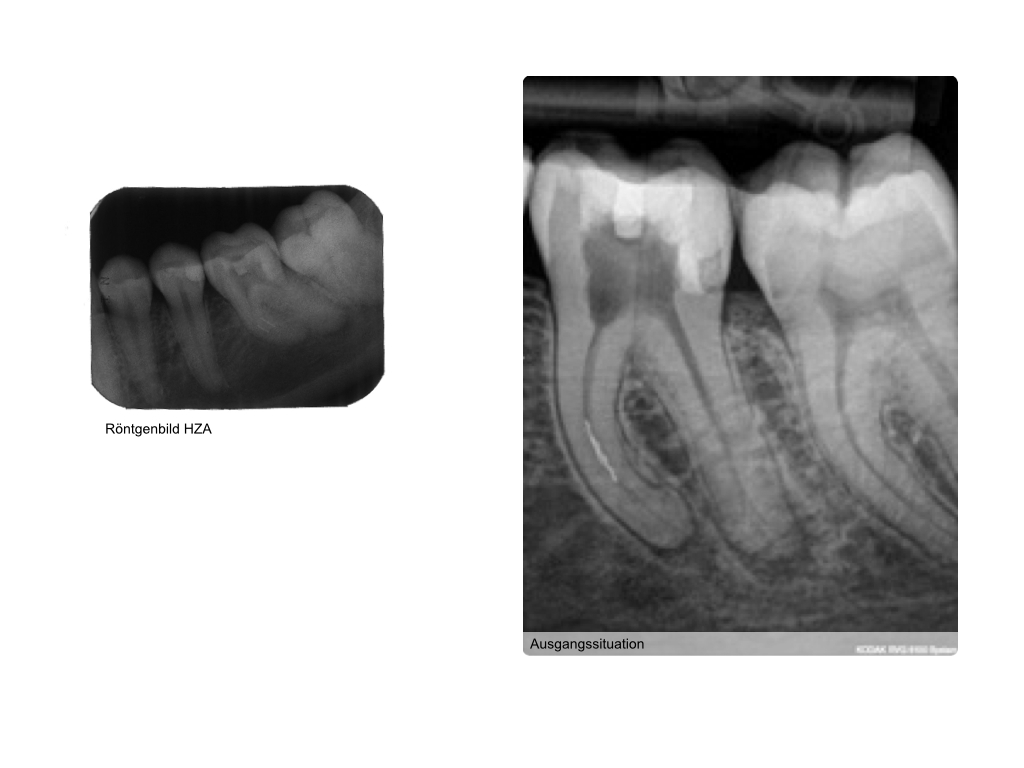

Instrumentenfrakturen (1)